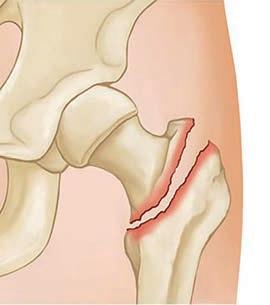

57 Cracking the case: negligence in missed neck of femur fractures

59 Report details the three steps to recovery from hip fracture